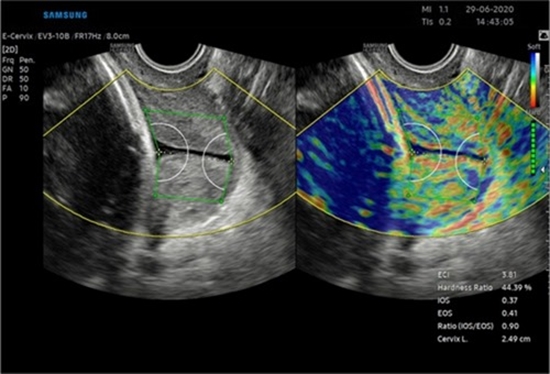

Diagnostic and clinical utility of ultrasound elastography for uterine cervical neoplasm

Purpose: Cervical cancer remains a major burden, especially in low-resource settings, due to limited screening. Traditional diagnostic tools, like colposcopy, are operator-dependent and often lack accuracy. Ultrasound elastography, including strain elastography (SE) and shear wave elastography (SWE), is a cost-effective, non-invasive tool for assessing tissue stiffness, aiding in distinguishing benign from malignant cervical lesions, and monitoring treatment. This review evaluates elastography's diagnostic accuracy and clinical utility in cervical cancer management.

Results: A total of twenty-three studies were included, with 19 in the meta-analysis. Elastography demonstrated high diagnostic accuracy for both detecting cervical cancer (sensitivity 88.3%, specificity 92%, AUC 0.965) and cervical intraepithelial neoplasia (CIN). SE trended to a non-significantly higher diagnostic accuracy than SWE (p = 0.51). Quantitative parameters differentiated cervical cancer from controls (SMD = 2.59, p < 0.001) and CIN (SMD = 1.75, p = 0.015). Elastography can effectively assess treatment response and tumor invasion.

Conclusion: Elastography aids cervical cancer diagnosis with high sensitivity and specificity, ideal for resource-limited settings due to its affordability and safety. Standardized training and guidelines are needed for consistent use. Future studies should compare SE and SWE, minimize variability, benchmark against MRI, and assess prognostic value